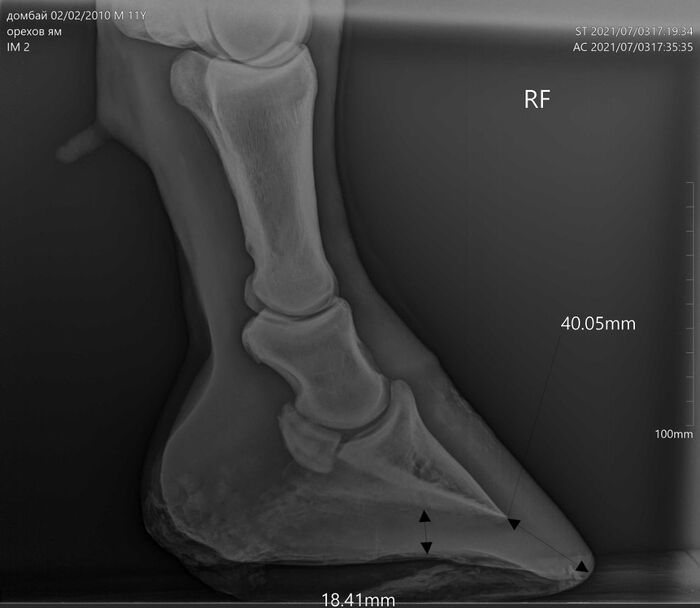

На этих x-ray снимках Домбай.

У него артроз (или артрит, я такой себе врач) пальчиков на руках.

Плюс косточка в копыте подходит очень близко к краю.

Из-за этого он все чаще и чаще страдает, иногда до коликов ( это когда от боли и стресса идет спазм ЖКТ и лошадь не может есть).